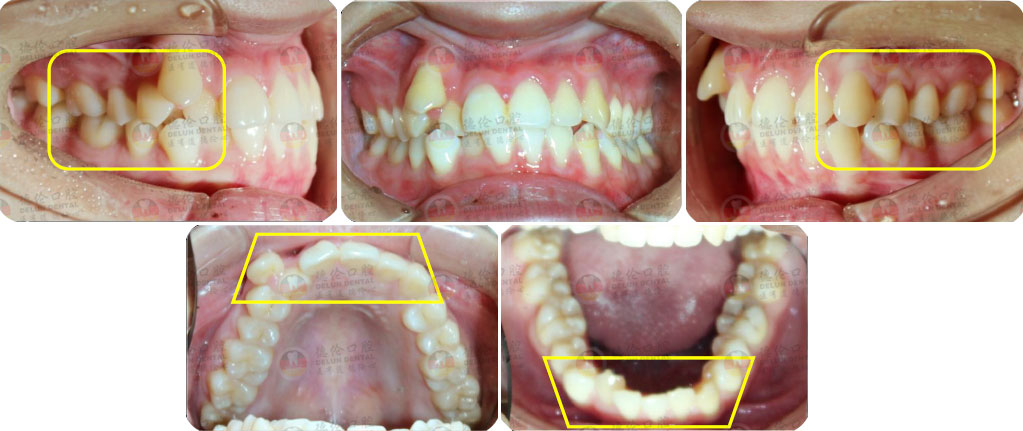

- 【診斷】

骨性I類,均角,安氏I類

上牙列重度擁擠,下牙列輕-中度擁擠

上中線右偏

13唇側(cè)錯(cuò)位

- 【治療方案】

拔除14,排齊上牙列

下頜尖牙適當(dāng)擴(kuò)弓,配合適量鄰面去釉,排齊下牙列

上頜左側(cè)配合適量鄰面去釉,調(diào)整中線

盡量調(diào)整后牙為尖窩咬合關(guān)系

矯治前后對(duì)比

蛻變周期:上頜16個(gè)月,矯治效率提升30%,下頜12個(gè)月,矯治效率提升20%